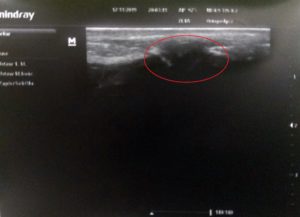

Kiểm tra siêu âm 2 tuần sau chấn thương: